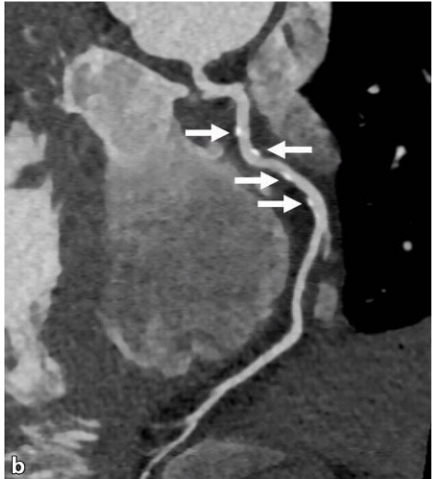

Aus Dänemark kommt eine interessante Studie zum Thema LDL, die einen neuen Blickwinkel auf die Entstehung eines Herzinfarkts oder einer arteriosklerotischen Herzerkrankung wirft. Man schaut mal nicht direkt per Blutmessung auf die Qualität der Blutfette oder des Insulin der Patienten, auch nicht auf die Oxidation und die Entstehung von Schaumzellen, sondern indirekt durch eine Koronarangiographie. So entstehen dann folgende Bilder, auf denen der Arzt feststellen kann, ob bereits Kalziumablagerungen entstanden sind oder nicht:

Die Studie von Mortensen mit über 20.000 Teilnehmern wurde daher unterschieden nach: Kalziumablagerung vorhanden (CAC>0) oder nicht vorhanden (CAC=0). Das gibt natürlich indirekt auch Auskunft über die Werte im Blut wieder, doch hier wurde eben ganz konkret nachgeschaut, welchen Zustand die Blutgefäße haben.